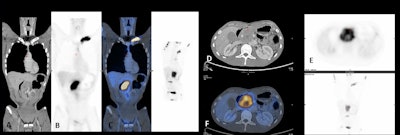

Epidural space is the compartment most often affected by hematological neoplasm and primary bone tumors, and multiple myeloma is the most common primary bone neoplasm and the most frequent primary bone tumor that may lead to spinal cord compression. In these cases, MRI is the gold standard for diagnosis and PET/CT plays an important role in staging or follow-up, depending on the neoplasm of origin, the researchers stated.

In bone lesions, whole-body CT is a good initial examination for patients who have multiple myeloma. "If there are one or more 5-mm or larger lytic myeloma lesions, there is no need for the patient to undergo further investigation, with the exception of complication assessment, or treatment response evaluation, where the PET/CT plays an important role," they noted.

PET is useful to distinguish benign from malignant MSK tumors because low uptake suggests that a bone lesion is likely to be benign (false negatives in plasmacytoma and low-grade chondrosarcoma).

In a known case of soft tissue lesion, PET is of some value in determining whether the lesion is benign or malignant and in grading malignant lesions. "Low uptake of FDG is of limited value in differentiating benign from malignant but high uptake usually indicates intermediate or high-grade malignancy. Radiographic correlation can often differentiate benign lesions with high uptake from sarcomas," they wrote.

Therefore PET is valuable in soft tissue malignancies for staging, guiding biopsy, detecting recurrence, therapy response, and tumor grading, and it is a standard modality for staging both Hodgkin's disease and non-Hodgkin's lymphoma. In Hodgkin's disease, PET can be of value in any stage, but it is most useful in stage 1 and 2 disease, where a change in the stage will alter disease management, the researchers pointed out.